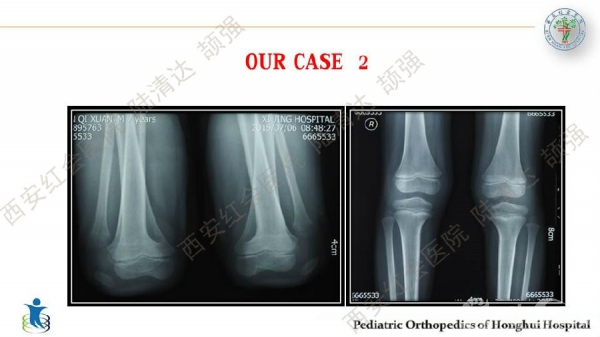

习惯性髌骨脱位,多见于儿童,女性多于男性。临床表现主要为行走步态难看、下肢无力、易摔跤等,而反复摔跤的病史常是患者就诊的主诉。其病理特点主要膝关节内外侧伸肌肌群不平衡及局部结构发育异常,表现为:股外侧肌及膝外侧软组织挛缩,髌韧带附着点偏外,股内侧肌群萎缩无力及MPFL发育不良,髌股关节滑车发育不良及膝外翻畸形等。习惯性髌骨脱位的治疗,建议早发现早治疗。不仅能有效解决脱位问题,还可避免继发畸形。如治疗延误,可出现髋、膝关节继发屈曲、腰前凸加大等畸形。甚至膝关节骨性关节炎,影响工作与生活。